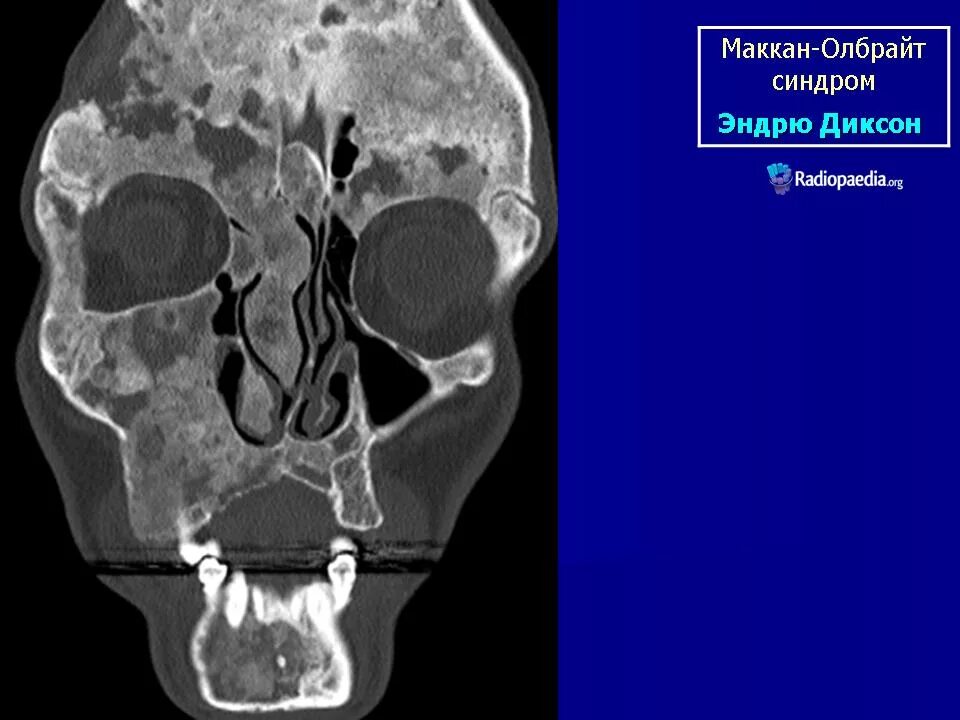

Синдром олбрайта